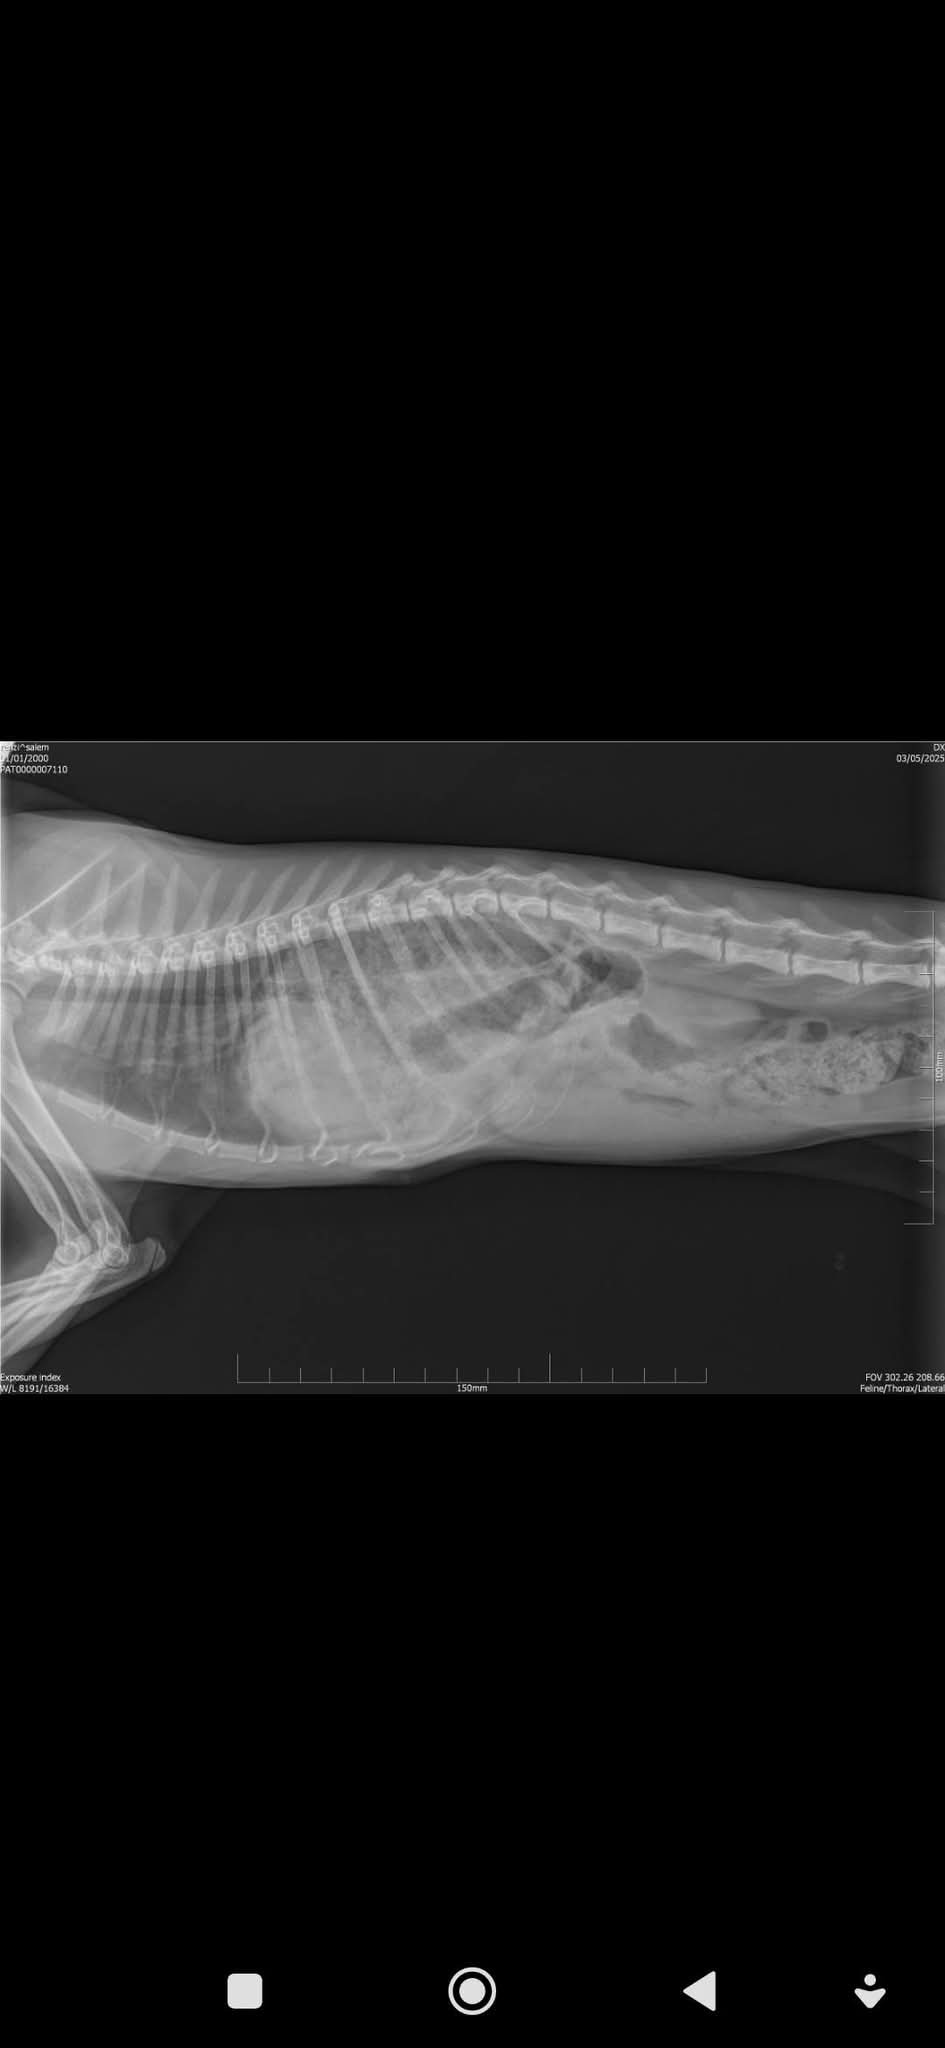

situazione e constatiamo che effettivamente un piccolo musetto nero con due occhi grandi e verdi, ci implora di tirarlo fuori da lì. Chiediamo l'intervento della polizia locale che, constatando la situazione emergenziale, attiva la procedura di recupero. Non è stato facile ma alla fine riusciamo ad entrare vediamo la situazione di completo abbandono di questa anima pura. Giorni e giorni, 10 per la precisione, senza cibo e acqua, solo poche crocchette che gli venivano tirate da uno spiraglio, uno scheletro coperto di pelo, 6 mesi circa, 1.2 kg di peso. Lo portiamo dal veterinario che constata la malnutrizione e la disidratazione. Viene preso in carico da una volontaria che lo cura con amore cercando di rimetterlo in sesto. La settimana scorsa mi chiama e mi dice di vedere Salem molto provato con una respirazione affannata, lo portiamo subito dal veterinario che conferma il nostro sospetto..ernia diaframmatica da trauma...va operato immediatamente. Ci cade il mondo addosso, Salem non ha finito di soffrire e sta rischiando la morte, è un'operazione molto invasiva e purtroppo molte volte con esiti mortali.Ora è in clinica e speriamo che domani, possa essere operato da un ottimo veterinario chirurgo dott. Giaconella e dalla sua equipe e speriamo che il suo esile corpicino (tutto pelo) non lo abbandoni.

Abbiamo bisogno del vostro aiuto per sostenere questa operazione che deve essere fatta con urgenza, purtroppo la situazione è grave , tutti i suoi organi addominali sono entrati nel torace e spingono sul suo cuoricino e sui polmoni, potrebbe soffocare in qualsiasi momento. Non si sa quale sia la causa, una caduta cercando di scappare dalla fame e sete, un calcio...mah non lo sapremo mai, quello che sappiamo è che con tutto il nostro amore, faremo l'impossibile per far risplendere quegli occhioni pieni di speranza.